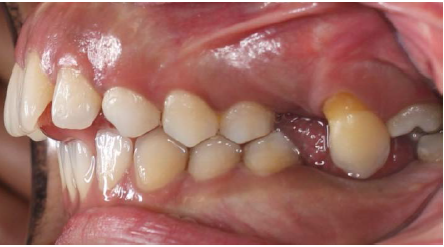

The intraoral examination revealed the transposition of the left maxillary canine that erupted mesial to the third molar (Figure 1). The distal slope of the canine was in contact with the mesial marginal ridge of the lower left third molar. The crown of the transpositioned canine was well-formed with a prominent cingulum (Figure 2).

Figure 1. Intraoral view of the canine erupting mesial to the third molar.

The right and left deciduous maxillary canines were retained. The rare occasional finding in this patient was the transposition of the left canine that erupted mesial to the third molar (Figure 1). The left first and second molars were absent. The patient did not remember anything about these teeth.